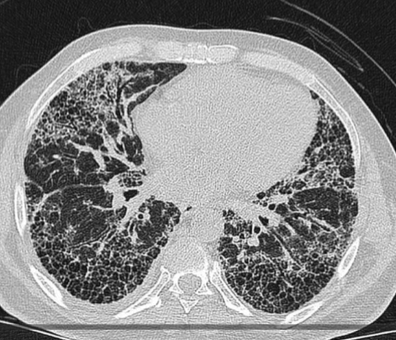

폐 섬유증은 폐에 염증이 반복되면서 정상적인 폐 조직이 점차 흉터 조직(섬유조직)으로 바뀌는 질환입니다. 이 섬유조직은 고무처럼 탄력이 없고 단단해, 한 번 형성되면 정상 폐로 되돌아가지 않는다는 특징이 있습니다. 이로 인해 폐가 충분히 팽창하지 못하고, 산소를 받아들이는 능력이 점점 떨어지게 됩니다.

이러한 변화 때문에 폐 섬유증은 단순 염증성 질환인 폐렴이나 기관지염과 달리, 진행성·비가역적인 폐 질환으로 분류됩니다.

폐 섬유증이란 한 번 손상되면 회복이 어려운 진행성 폐 질환입니다. 하지만 조기에 발견해 치료를 시작하면 진행 속도를 늦추고 삶의 질을 유지할 수 있습니다.

✔ 흉부 CT에서 이상 소견이 나온 경우